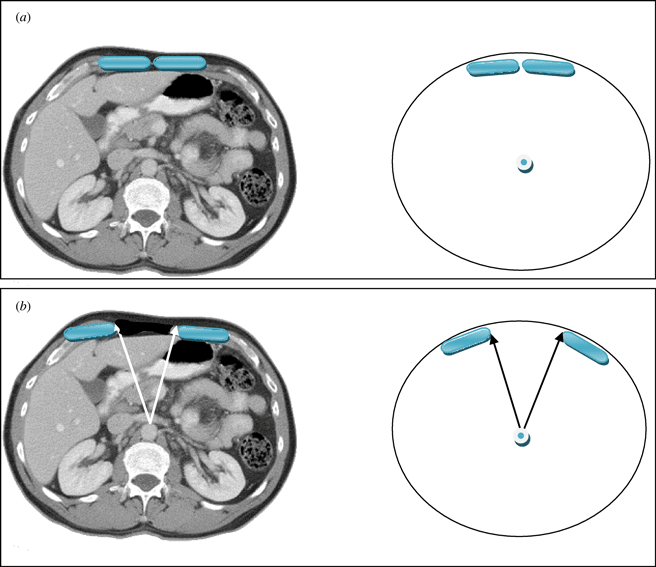

The vertical midline incision via the linea alba remains the standard technique for abdominal surgery. Incidence of herniation after midline laparotomy varies in reports from 2% to 11%.1,2 Early reports of reconstruction of these deficits with direct closure techniques yielded disappointing results, with failure rates of up to 50%.3 To address these results several authors published techniques utilizing the multilayered myofascial envelope of the abdominal wall to alleviate the tension in abdominal wall closure.4-11,13-42 The Component Separation technique for repair of ventral hernias was first described by Ramirez et al in 1990.4 This was a formal description of a selective release of abdominal fascia to assist with closure of ventral hernias. The technique includes separation of the rectus abdominus muscle from the external oblique muscle with dissection in the avascular plane between the external oblique and the internal oblique muscles. Since that time there have been several developments regarding the technique, and several variations of the procedure have been described.5-8 Several large reviews of the literature also detail methods of component separation and comparisons of outcomes with various types of mesh.18,19,21,23,25-30 The benefits of this procedure focus on its use of innervated, vascularized, autologous tissue for the reconstruction of the abdominal wall. In addition, beyond providing for a reduction in tension, the use of these innervated, myofascial flaps helps to recreate the dynamic nature of the native abdominal wall. These and other reconstructive strategies have contributed to a body of literature citing a recurrence rate now averaging 10% to 15%.5-7 Preoperative assessment of the ventral hernia patients reveals significant loss of domain, poor quality of the surrounding skin and soft tissue envelope, and a significant rectus muscle diastasis. One of the challenges when planning an abdominal wall reconstruction is predicting the need for interpositional mesh repair versus performing a component separation to achieve midline closure. In an attempt to address this problem, we are proposing the Component Separation Index (CSI), a calculated value based on the preoperative computed tomographic (CT) scans of these patients. The concept of an index value is seen throughout the medical literature, examples of which include the ankle-brachial index used in vascular surgery and the body mass index used in bariatric surgery. These values arose out of the need to quantify biometric data and provide a useful objective value for preoperative evaluation, comparison, or as predictors of outcomes. Regarding repair of large ventral hernias, rather than relying only on the distance between the edges of the hernia or the total square centimeters of the defect, the CSI utilizes a value based on a preoperative CT scan of the abdomen with the angle of diastasis of the rectus musculature with the vertex based at the aorta. This is then placed as a comparator over 360°. The value of the angle of diastasis takes into account not only the transverse dimension of the hernia but also the AP dimension of the patients' unique body habitus providing an added dimension of the patients' biometric identity. (Figs 1 and 2)

The angle of diastasis

This angle was measured from the preoperative CT scans obtained for each patient included in the study. The vertex of the angle was taken as the position of the aorta at the axial CT image where the maximal transverse dimension of the hernia defect was identified. The arms of the angle were then taken from this point to the medial edges of the rectus abdominus muscles (Figs 1 and 2).